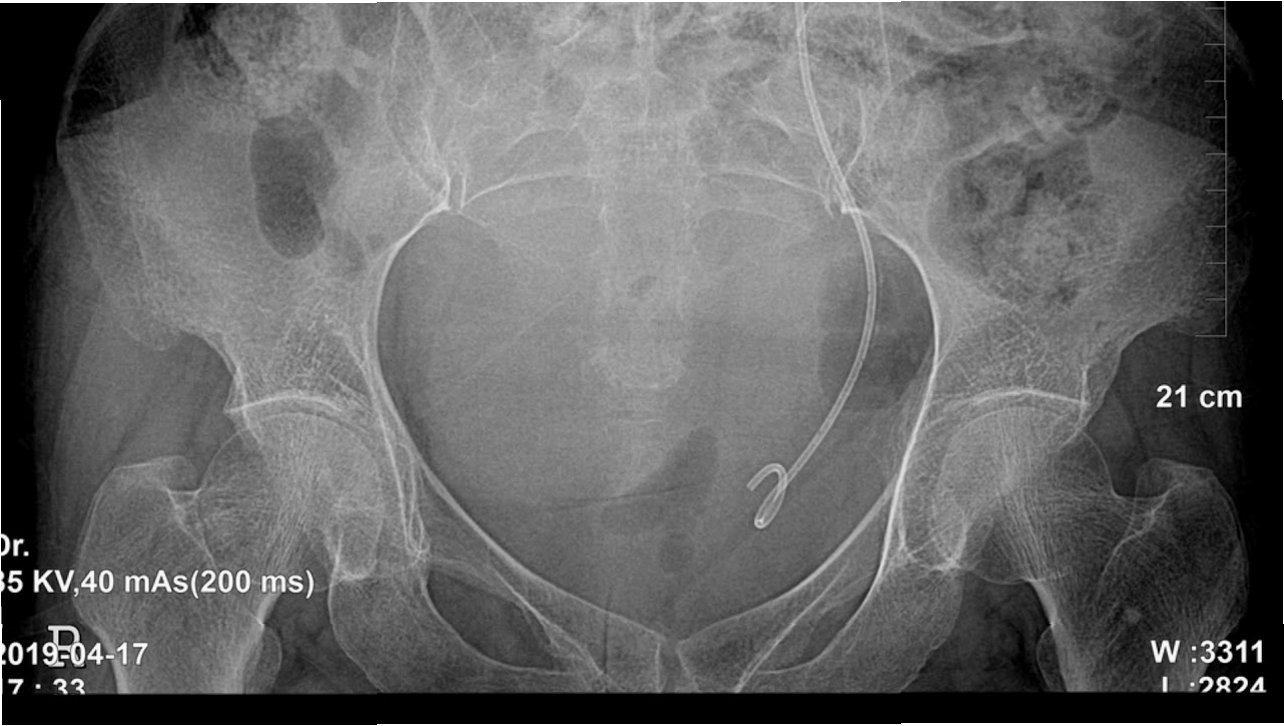

요로결석 수술을 결정하기 전에, 정확한 진단과 평가가 필수적입니다. 먼저, 환자의 병력 청취와 신체 검사를 통해 결석의 위치와 크기, 그리고 환자의 건강 상태를 파악합니다. 소변 검사, 혈액 검사, 영상 검사(X-ray, CT) 등을 통해 결석의 종류와 요로계의 해부학적 구조를 확인합니다. 이러한 검사 결과를 바탕으로, 환자에게 가장 적합한 수술 방법을 결정하게 됩니다. 수술 전에는 금식, 혈압 조절 등 수술에 필요한 기본적인 준비가 이루어집니다.

2. 요관 내시경 수술(URS): 요도, 방광을 거쳐 요관 내시경을 삽입하여 결석을 직접 제거하거나 레이저로 분쇄하는 방법입니다. 결석의 위치에 관계없이 비교적 효과적으로 결석을 제거할 수 있으며, 빠른 회복을 기대할 수 있습니다.

3. 경피적 신절석술(PCNL): 옆구리에 작은 절개를 통해 신장으로 접근하여 결석을 제거하는 방법입니다. 크기가 크거나 복잡한 형태의 결석 제거에 효과적이지만, 침습적인 수술이므로 합병증의 위험이 있습니다.